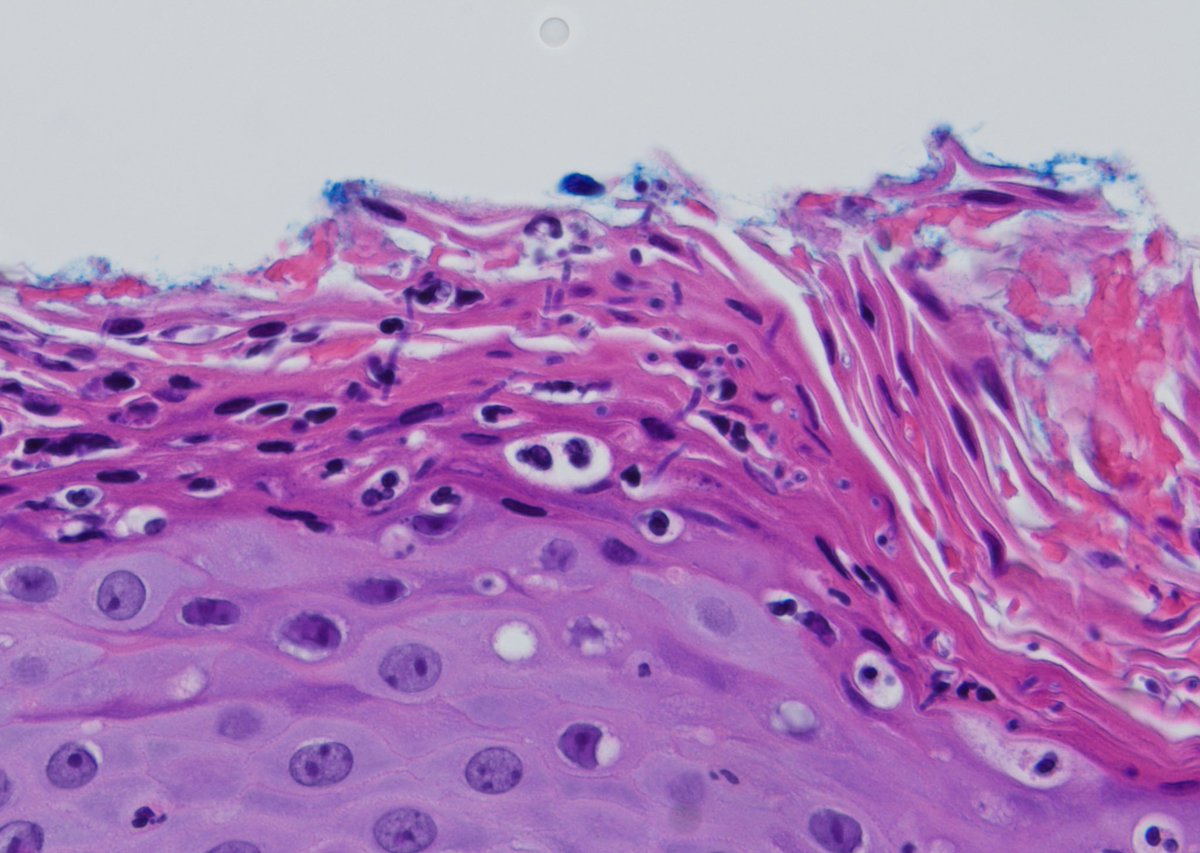

Pagetoid? Confluence? Regression? Measuring Breslow? Learn tips & tricks for diagnosing #melanoma including examples of multiple subtypes in this 101 video: kikoxp.com/posts/3764. #dermpath #dermatology #dermatologia #dermtwitter #pathologists #pathology #pathTwitter